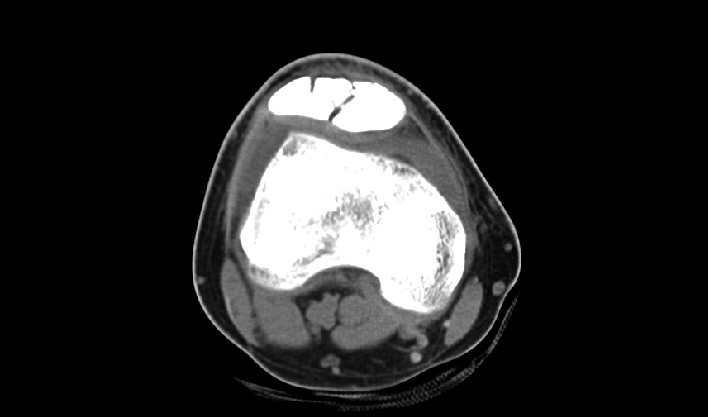

La matriz de reconstrucción de 1024*1024 amplía los datos de la imagen cuatro veces. Combinado con imágenes de corte fina, incluso las lesiones más invisibles son claramente visibles.